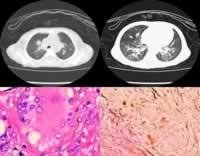

正常肝臟中此酶的活力最高,肝、腎、腦小腸亦富於此種酶。此病患者的肝、脾等組織中酶的活力降低至50%以下。患兒全身網狀內皮系統中可查見富含脂類的直徑為20~90μm的大型泡沫細胞,以脾、骨髓、肝、肺和淋巴結等部位為主。這種泡沫細胞又稱為尼曼-匹克細胞,通常僅見一個偏位的小細胞核,染色質疏鬆;胞漿充滿脂類小滴(胞質體),在未染色片上呈“桑葚”狀,Giemsa染色時,胞漿呈藍或藍綠色,內有深淺不一的藍色顆粒。不同於Gaucher細胞的是:酸性磷酸酶染色呈弱陽性;Schultz反應(檢測膽固醇)呈陽性。亦可用位相顯微鏡或電鏡檢查鑑別兩者。

急性神經型

尼曼匹克氏病臟器結果 (A型或嬰兒型):為典型的尼曼-匹克(占85%),多在生後3~6月內,少數在生後幾周或1歲後發病。初為食欲不振、嘔吐、餵養困難、極度消瘦,皮膚乾燥呈臘黃色,進行性智力、運動減退,肌張力低軟癱,終成白痴,半數有眼底櫻桃紅斑(cherryred spot)、失明,黃疸伴肝脾大。貧血、惡液質,多因感染於4歲以前死亡。皮膚常出現細小黃色瘤狀皮疹有耳聾。神經鞘磷脂累積量為正常的20~60倍,酶活性為正常的5~10%,最低